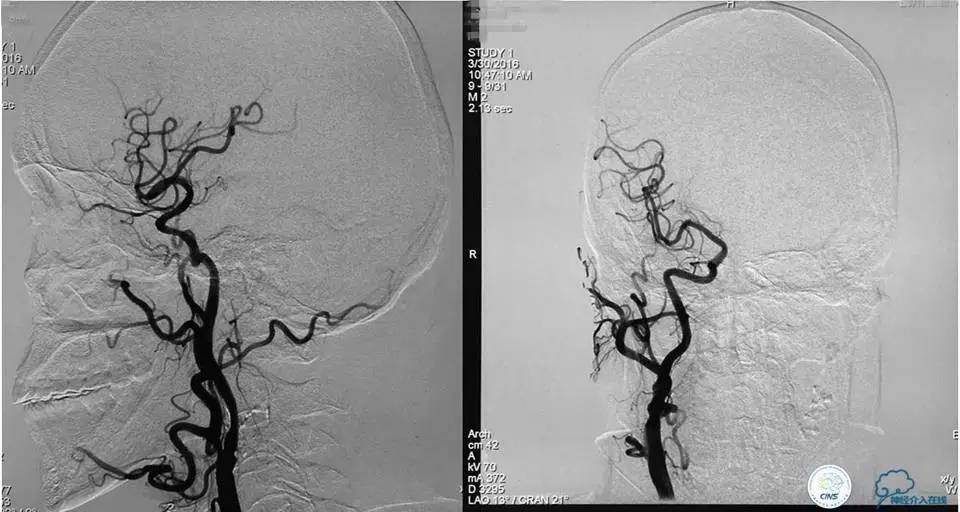

术后工作位造影

术后右斜位和左斜位造影显示动脉瘤完全栓塞